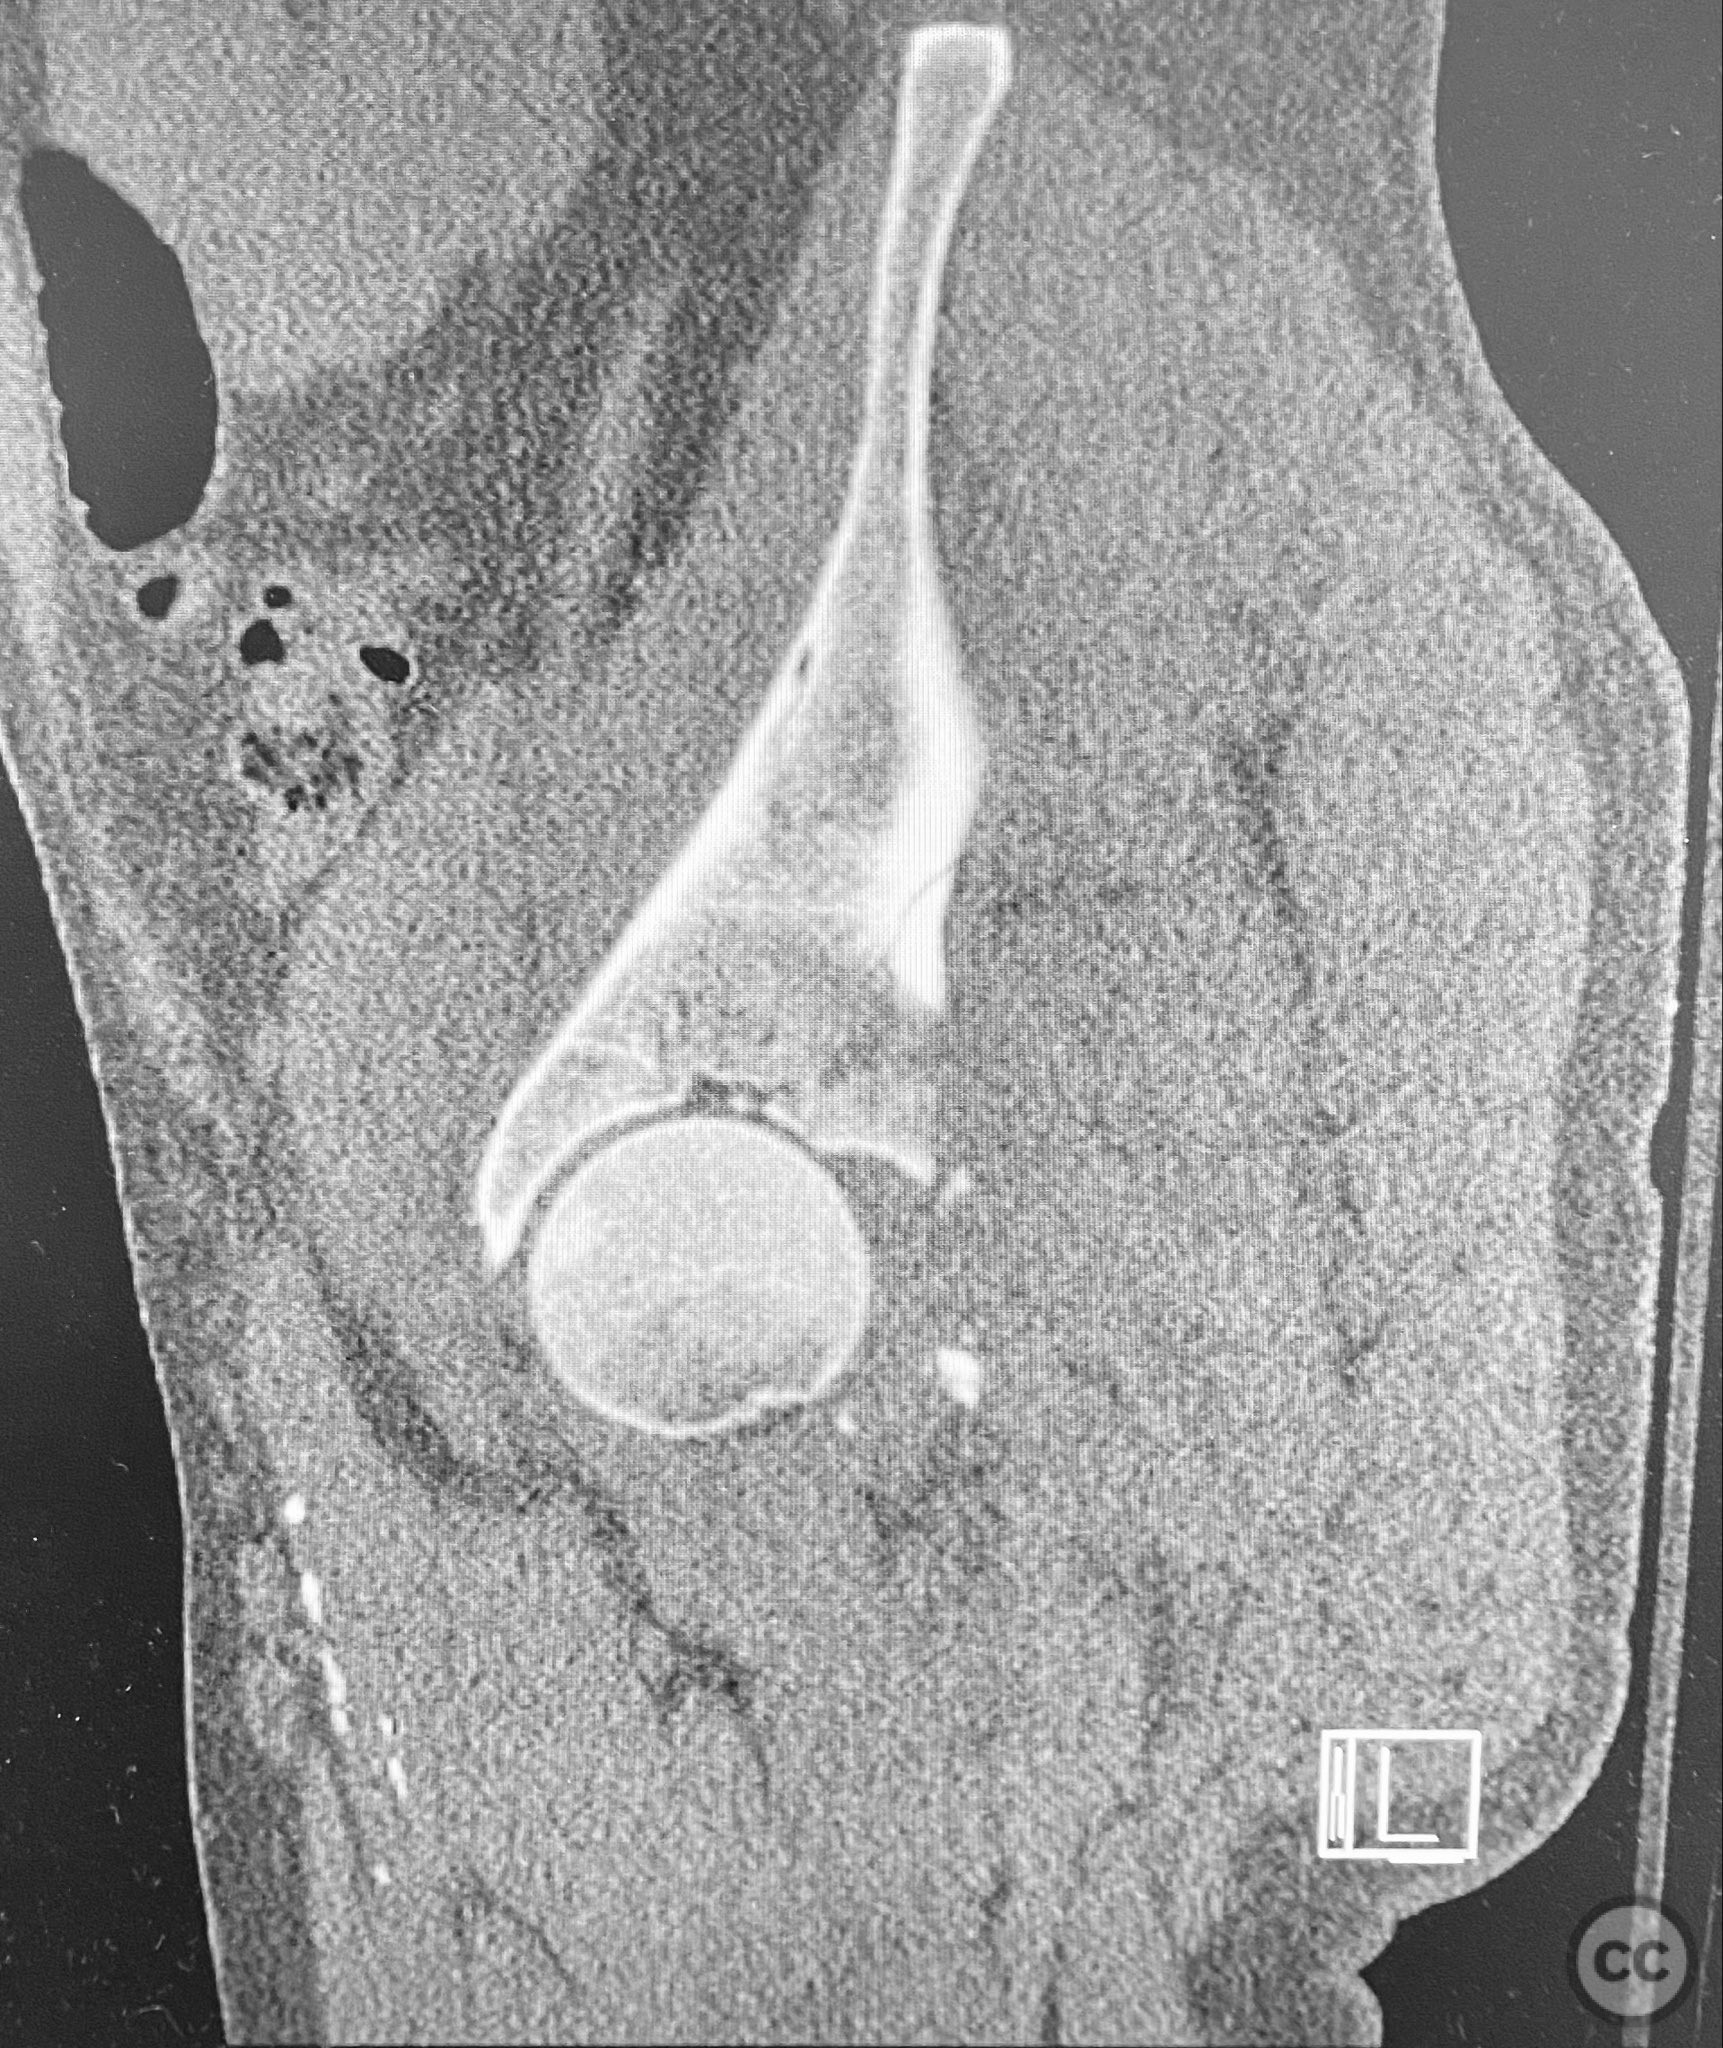

Clinical and radiological findings:  A patient presented with a seemingly non-comminuted, wide, and long posterior wall (PW) acetabular fracture fragment. Axial computed tomography (CT) images demonstrated the thickness of the PW fragment, the articular surface, and multiple areas of subchondral impaction. Preoperative planning identified the size, location, and depth of the impaction zones, as well as an essentially nondisplaced transverse acetabular fracture line, which was not readily apparent on initial imaging. No significant displacement of the transverse component was noted. The AO/OTA classification is 62-B1.3 (posterior wall and transverse acetabular fracture).

Planning remarks:  The preoperative technical plan included a prone Kocher-Langenbeck (KL) approach to access the posterior column and wall. The plan entailed elevation and reduction of impacted articular fragments, bone grafting of subchondral defects, anatomical reduction and provisional fixation of the posterior wall fragment, and definitive fixation with a contoured plate. Intraoperative fluoroscopy was planned to guide additional screw placement through the plate to stabilize both the posterior wall and the transverse fracture line. A supplementary medial plate was planned to augment fixation of both the posterior wall and transverse components.